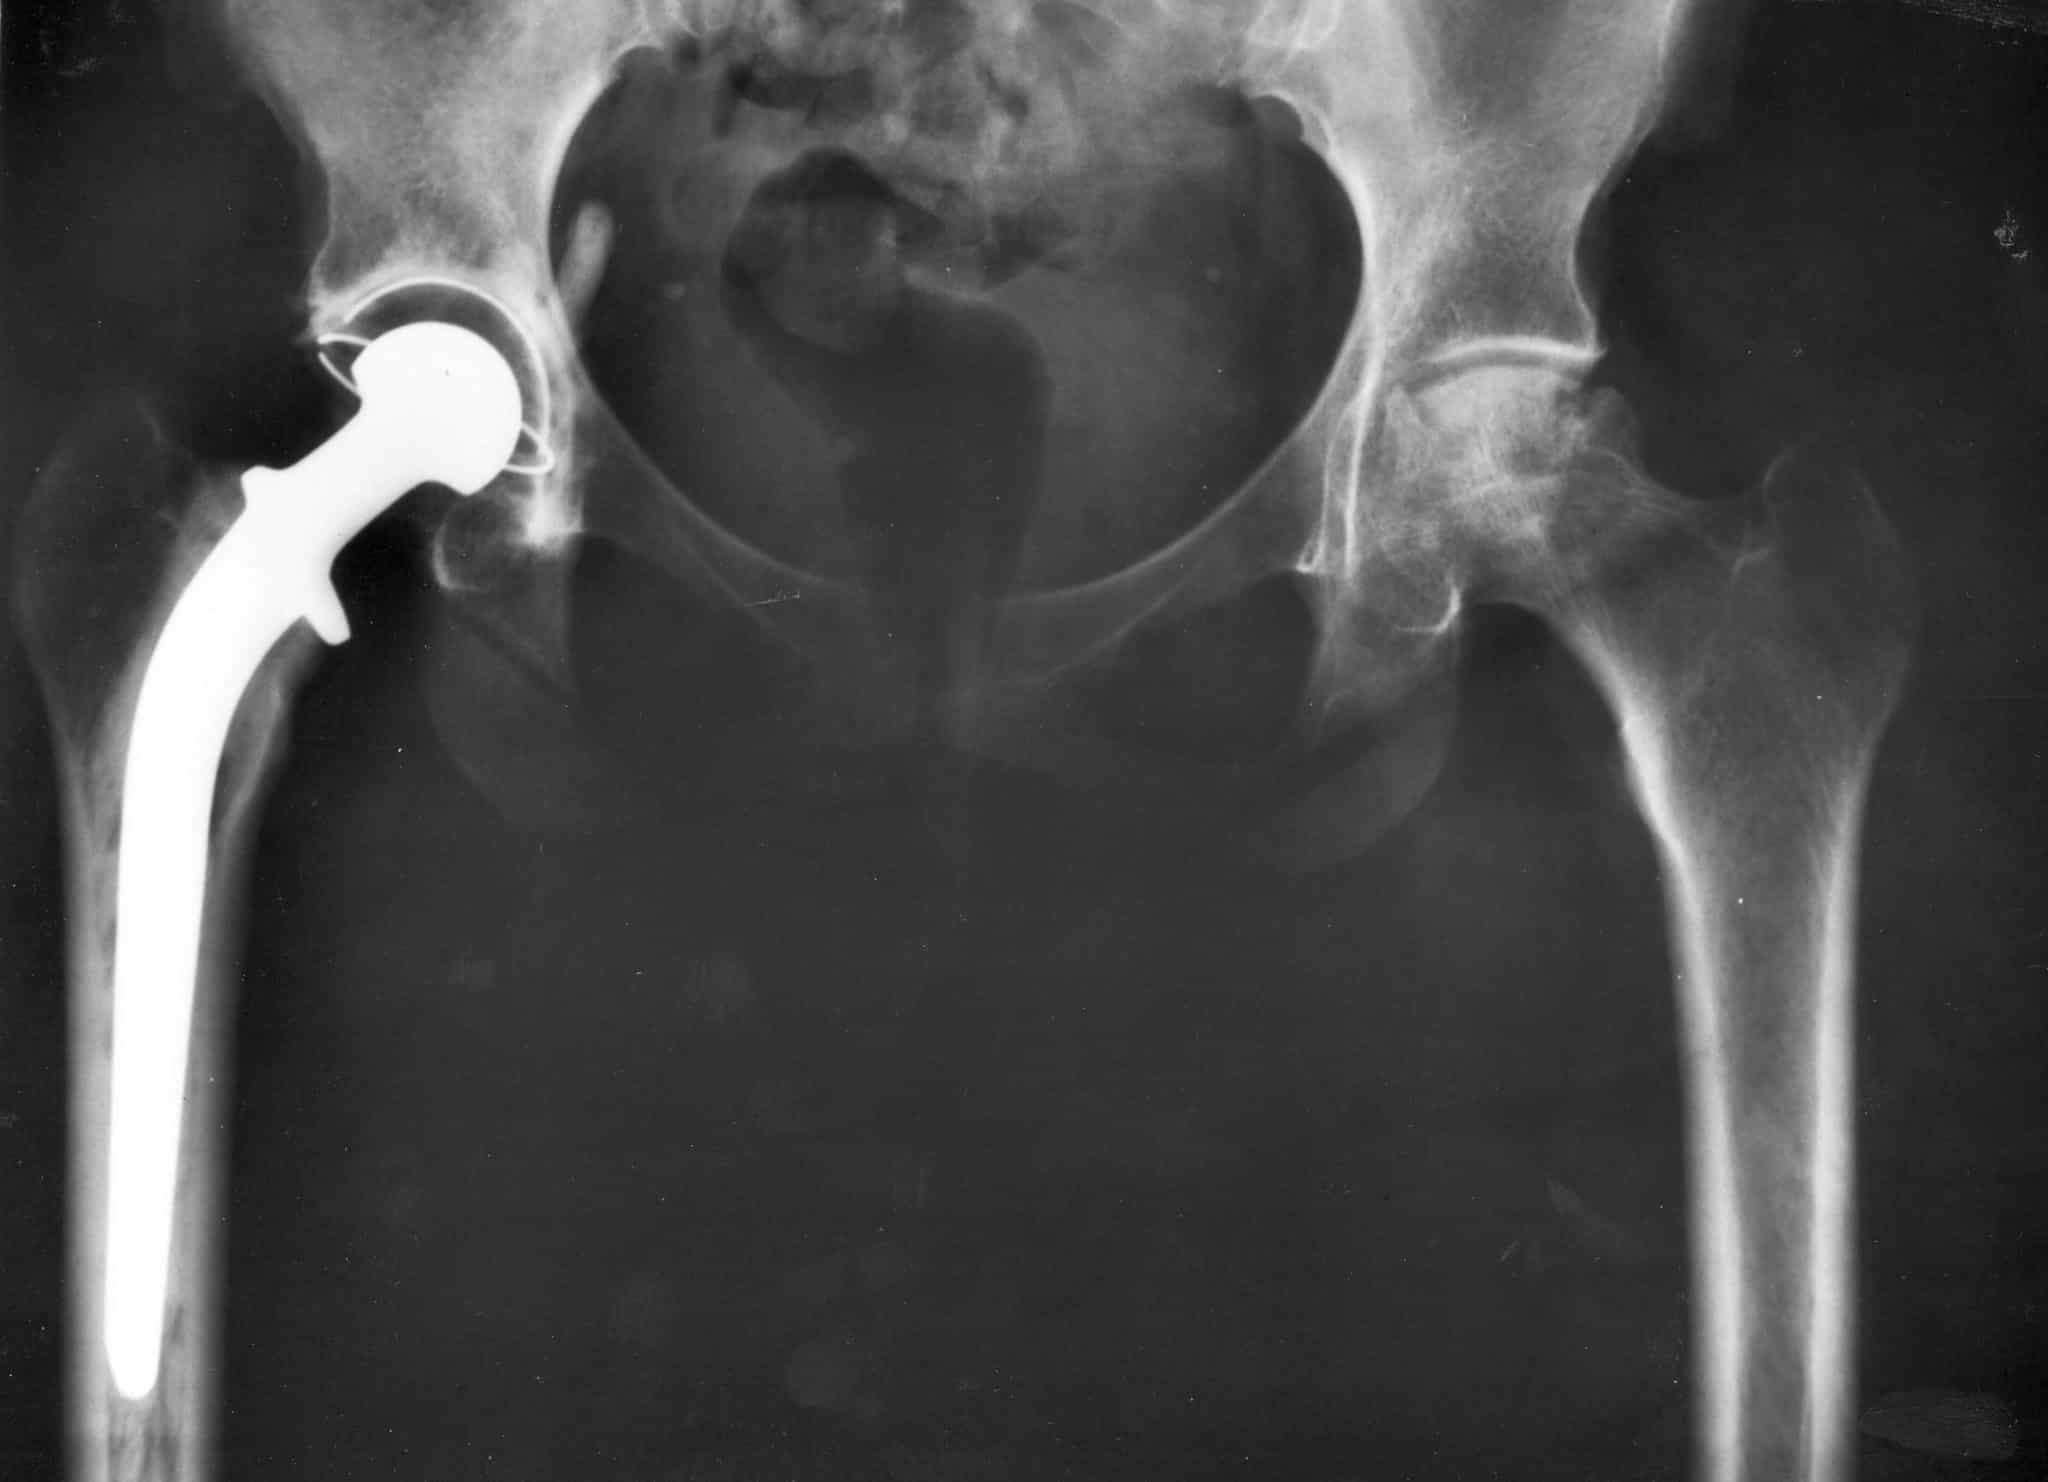

Современная медицина достигла значительных результатов в области замены поврежденных суставов. Подобные операции сегодня стали высокоточными процедурами, позволяющими пациентам не просто избавиться от хронической боли, а вернуться к полноценной активной жизни. По последним данным, примерно 200 тысяч человек в России ежегодно нуждаются в полной замене тазобедренного сустава. Такая потребность делает важным не только доступность самой операции, но и создание имплантатов, которые служили бы десятилетиями без риска отторжения и повторных операций.

Проблема в том, что существующие металлические протезы остаются чужеродными для организма. Большинство материалов, которые используют врачи, в 4-5 раз жестче натуральной кости. Эта разница приводит к медленному разрушению тканей вокруг имплантата, его расшатыванию и необходимости повторной операции.

Более перспективным решением считаются углерод-углеродные композиты. Это искусственные материалы, созданные специально для медицины, которые сочетают высокую прочность с упругостью, близкой к натуральной кости. Их особенность в том, что под нагрузкой они образуют в своей структуре множество микротрещин и пор. Это способствует лучшему приживлению протеза, поскольку организм начинает заполнять появившиеся пустоты костной тканью, превращая искусственный протез в «естественную» часть скелета. В результате использование углеродных материалов предотвращает отторжение имплантата и продлевает его срок службы.

Однако до сих пор инженеры не могли точно рассчитать, как изменится прочность протеза после того, как в него прорастет кость. Это знание критически важно, поскольку оно позволяет предсказать, как долго и насколько надежно он будет служить пациенту после операции.

До сих пор такие протезы создавались исходя из предположения о том, что костная ткань полностью и равномерно заполняет все пустоты и трещины в композитном материале. Но ученые Пермского Политеха выяснили и доказали, что в реальности этот процесс намного сложнее. В отличие от старых подходов, которые давали усредненный и завышенный прогноз срока службы протеза, результаты исследователей ПНИПУ максимально приближены к тому, что происходит в теле пациента. Это позволит создавать более долговечные имплантаты и точнее прогнозировать их приживаемость. Статья опубликована в журнале «Российский журнал биомеханики».